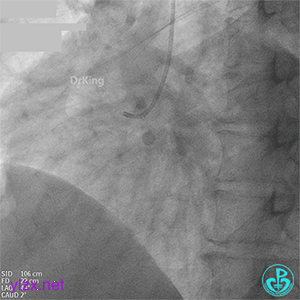

03 急诊冠脉造影

右冠脉粗大,近中段瘤样扩张明显,中段闭塞,局部可见大块血栓影。

前降支开口至近段明显瘤样扩张,中段闭塞,第一对角支粗大,无明显狭窄。

LCX发育小,内膜不光滑,血流3级。

首选开通右冠脉,导丝到达闭塞段远端,球囊扩张后,可见大量血栓,抽吸导管反复抽吸出大量血栓。冠脉内推注尿激酶原20mg,复查造影提示右冠脉远端显影,调整导丝至远段。

球囊再次扩张闭塞段,并对后降支及左室后支开口行对吻球囊扩张,复查造影示血流3级,无夹层行成,右冠脉远段仍可见血栓影。